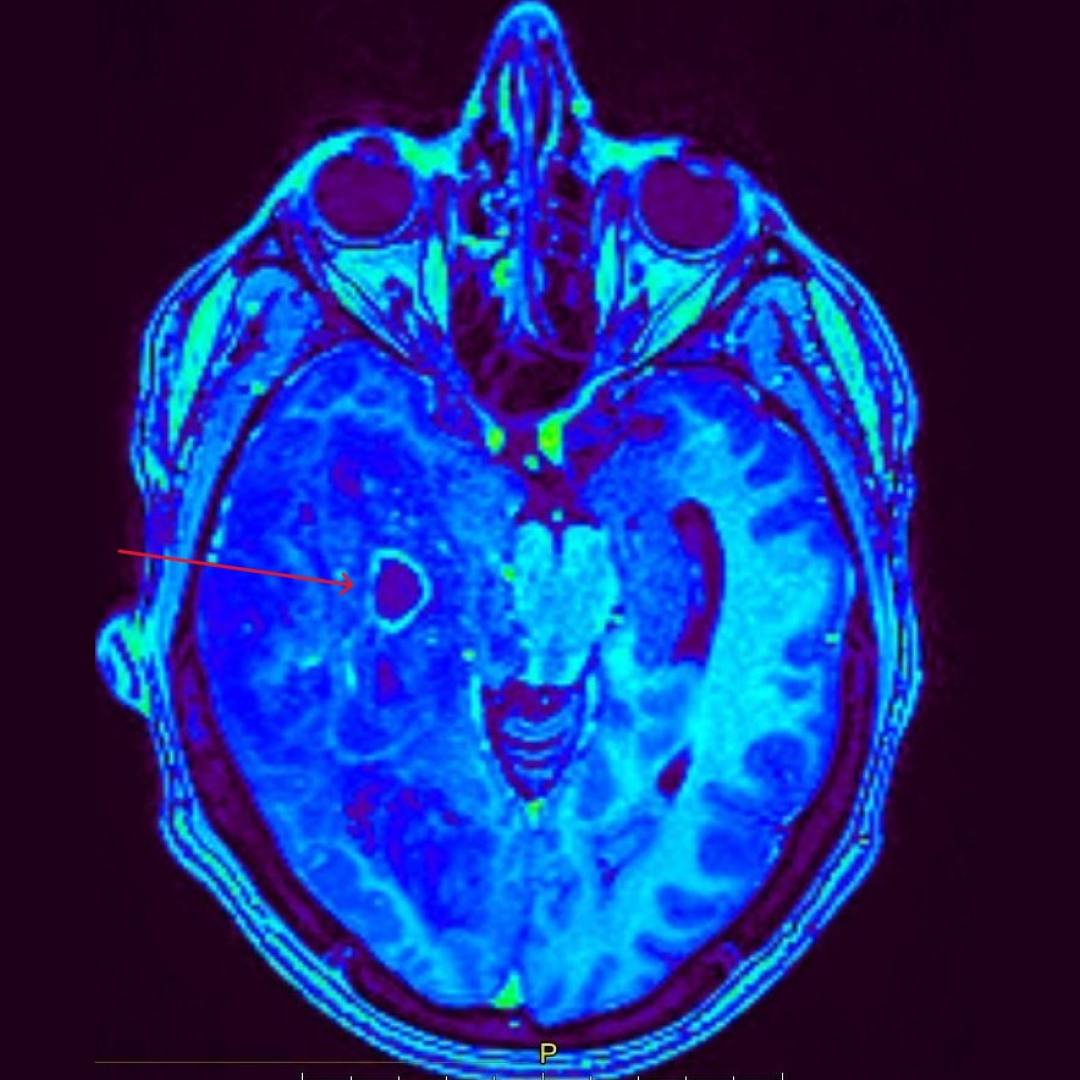

При проведении МРТ головного мозга выявлена опухоль правой височно-теменной области с переходом на островок, вовлечением базальных ядер справа и мозолистого тела с выраженным перифокальным отеком с дислокацией срединных структур мозга влево, компрессией правых бокового и третьего желудочков, среднего мозга.

При введении контрастного препарата визуализировался участок интенсивного кольцевидного накопления по периферии кистозного компонента опухоли.